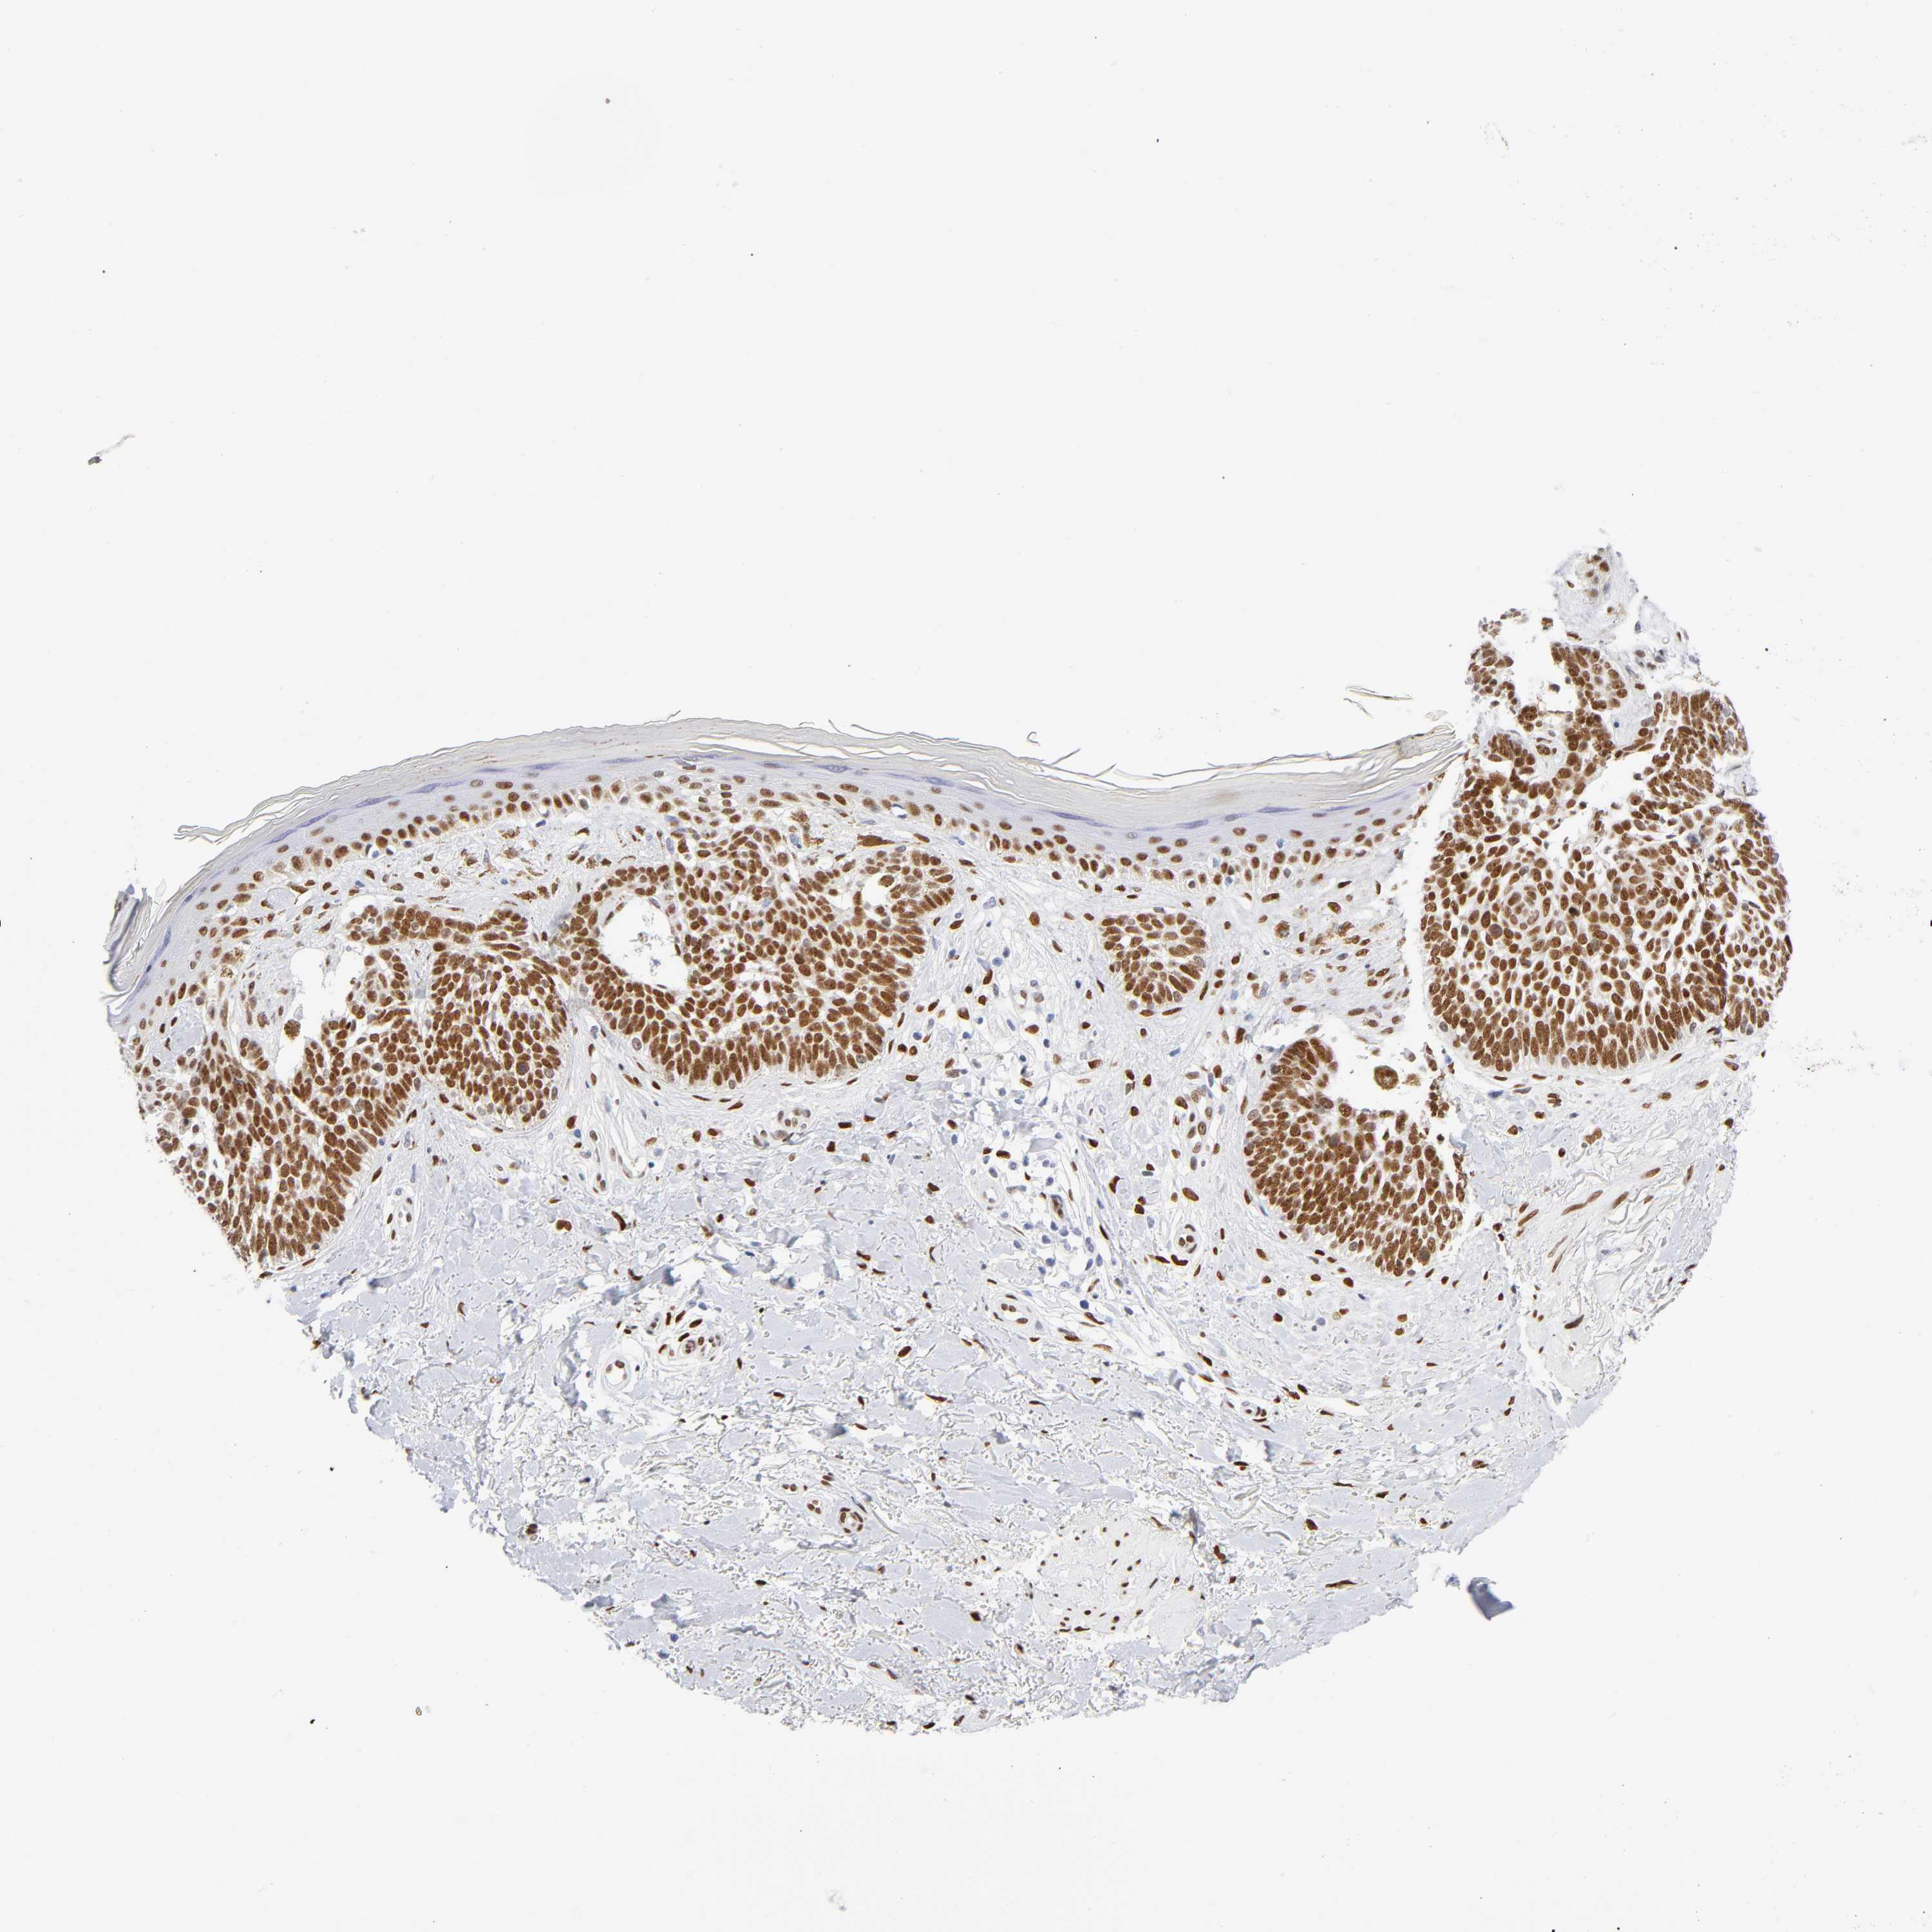

SKIN CANCER - Protein expressioni

A mouse-over function shows sample information and annotation data. Click on an image to view it in a full screen mode. Samples can be filtered based on level of antibody staining by selecting one or several of the following categories: high, medium, low and not detected. The assay and annotation is described here.

Antibody stainingi

Antibody staining in the annotated cell types in the current human tissue is reported as not detected, low, medium, or high, based on conventional immunohistochemistry profiling in selected tissues. This score is based on the combination of the staining intensity and fraction of stained cells.

Each image is clickable and will lead to virtual microscopy that enables deeper exploration of all samples and also displays staining intensity scores, fraction scores and subcellular localization as well as patient and tissue information for each sample.

Antibody HPA052625

Staining

High

Medium

Low

Not detected

Intensity

Strong

Moderate

Weak

Negative

Quantity

>75%

75%-25%

<25%

None

Location

Nuclear

Cytoplasmic/membranous

Cytoplasmic/membranous,nuclear

Basal cell carcinoma

BCC, low aggressive